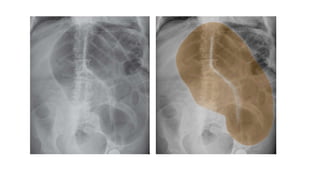

SOLID ORGAN ENLARGEMENT

Either by increase in the overall size of one of the solid organs or by a large

RADIOLOGICAL SIGNS :

•Large soft tissue density (light grey)mass

•Loops of bowel often displaced by the mass

•Location gives a clue

RUQ – liver , right kidney

LUQ – spleen ,left kidney , fluid filled stomach

Lower abdomen – ovaries,uterus , distended urinary bladder.